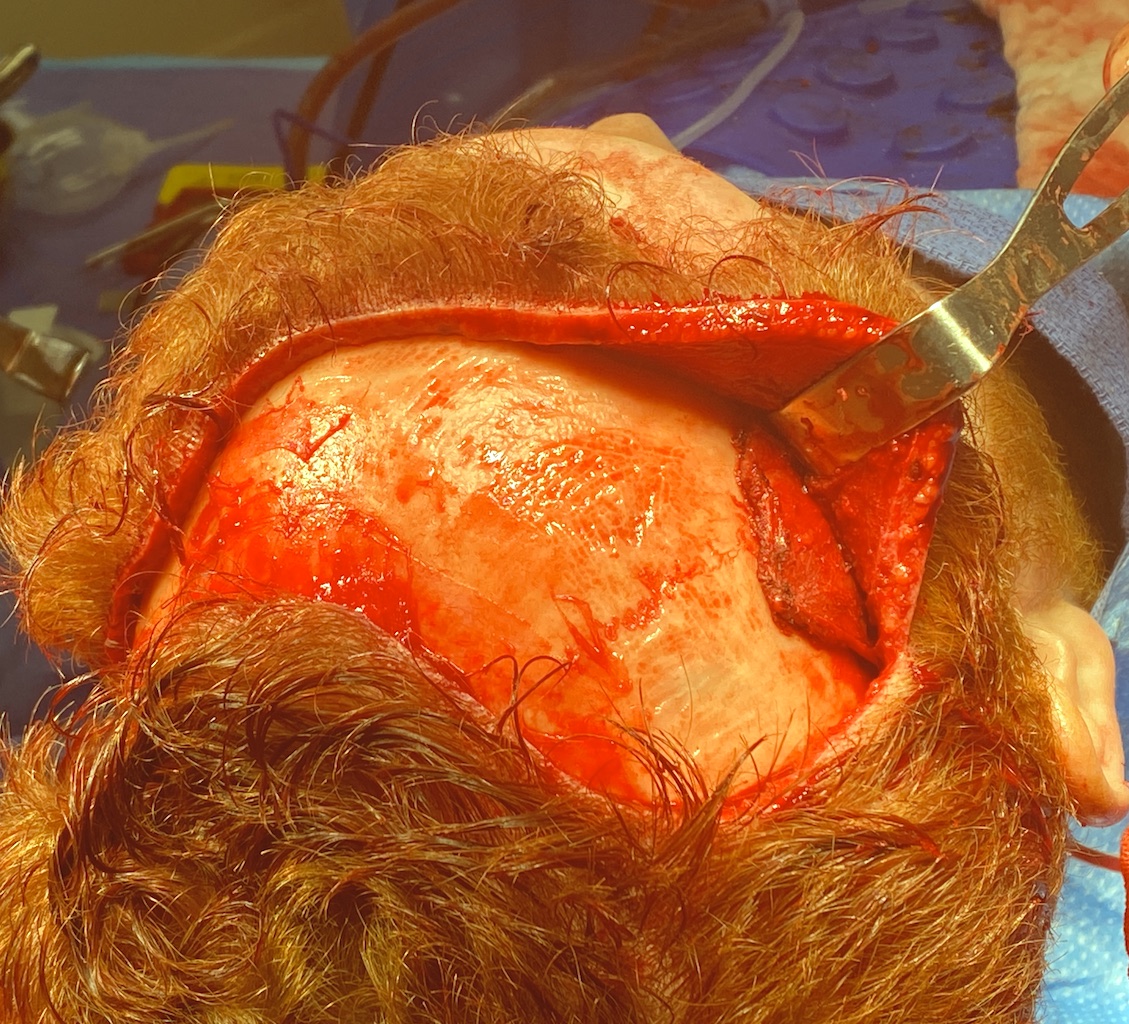

Patient 47

Desire for reduction of prominent occipital knob deformity.

Intraoperative result from occipital knob skull reduction through a direct small scalp incision.

Desire for reduction of prominent occipital knob deformity.

Intraoperative result from occipital knob skull reduction through a direct small scalp incision.